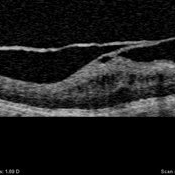

Posterior Vitreous Detachment

Left: Preset lens biomicroscopy of PVD in the left eye of a subject with a widely dilated pupil. The detached posterior vitreous cortex is seen (arrows) as is the optic disc and retinal vasculature (upper left). (courtesy of C. L. Trempe MD, Harvard Medical School, Boston, MA) [Sebag J: Vitreous – in Health & Disease Springer, New York, 2014; image © Springer Nature, reprinted with permission] Right: B-scan ultrasonography of PVD images the detached posterior vitreous cortex with a visible Weiss Ring.

Condition/keywords: posterior vitreous detachment